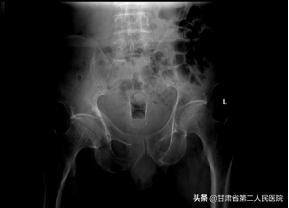

放支架一周后拍片